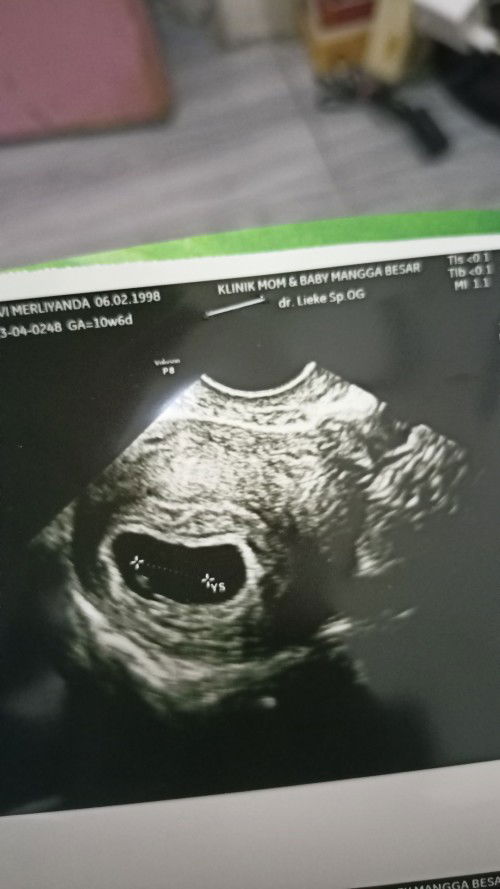

Bun saya mau tanya saya usg Uda 7 Minggu tapi belum ada janinny .

Hamil 7 Minggu

Izin ya bun, itu kantungnya udah gede banget. Kalo menurut medis kantung >2,5 cm harusnya udah ada janin dan kedeteksi djj. Kalo dari dokternya bagaimana ya bun? Karna aku kemaren seperti itu dan diagnosis BO ๐๐ป. Coba nanti di tunggu dulu 2 minggu bun usg lagi semoga ada perkembangan

kalo kt dokter saya wajar aja bund, perkembangan janin beda2.. tp kata dokter kl udh 11 week belom terlihat juga baru bisa dikatakan BO. sehat2 terus yaa bund

aku 6w allhamdulillah udah ada bund, coba minta penjelasan bund apa ada indikasi lain seperti BO dan di kertas usg nya 10w bund?

normal ada yg 10week baru keliatan bund. yg penting tetep makan bergizi dan minto asam folat tiap hari ya. boleh USG lagi stelah 10week

7minggu sesuai hpht ga bun? Biasanya beda kaya aku.. Coba ditunggu ya bun smg Next usg sdh ada janin nya. Semangat๐

sama kaya aku mba? barusan usg trasv kantung nya uda besar, tp blm ada janin. dokter bilang disuru balik lagi 1 munggu ini

Saya juga 7minggu, usg masih kantong aja. Dikasih obat penguat dan disuruh 2minggu lg usg. Semoga aman2 ya bunn

itu kyknya kok udh ada bun kecil di ujung, soalny aku 7week jg dblg gk ada janin eh ternyata di ujung persis kecil